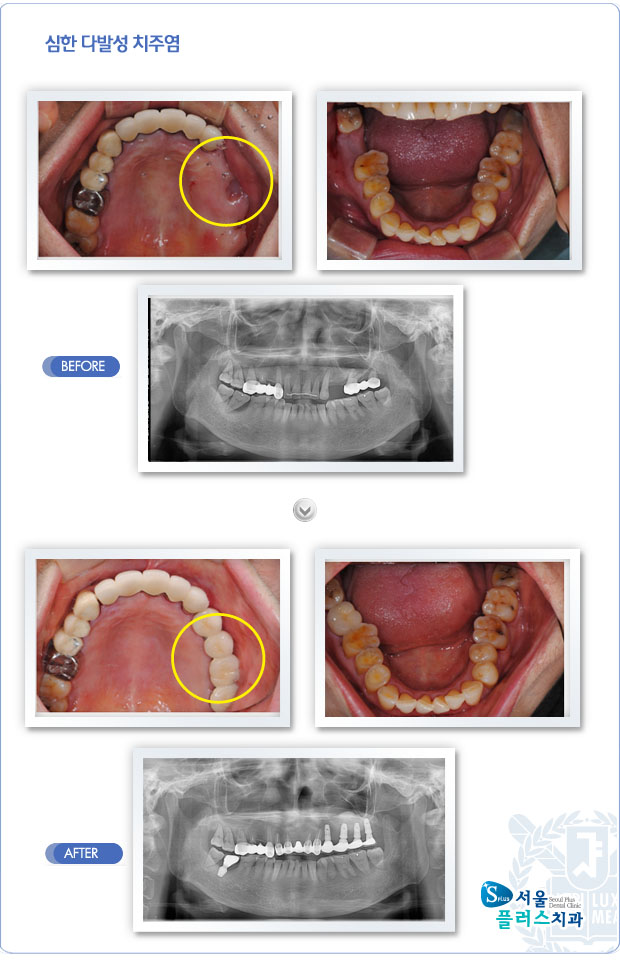

[임플란트] 심한 다발성 치주염